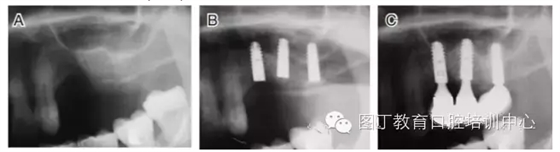

病例3 有骨間隔(圖5)

圖5